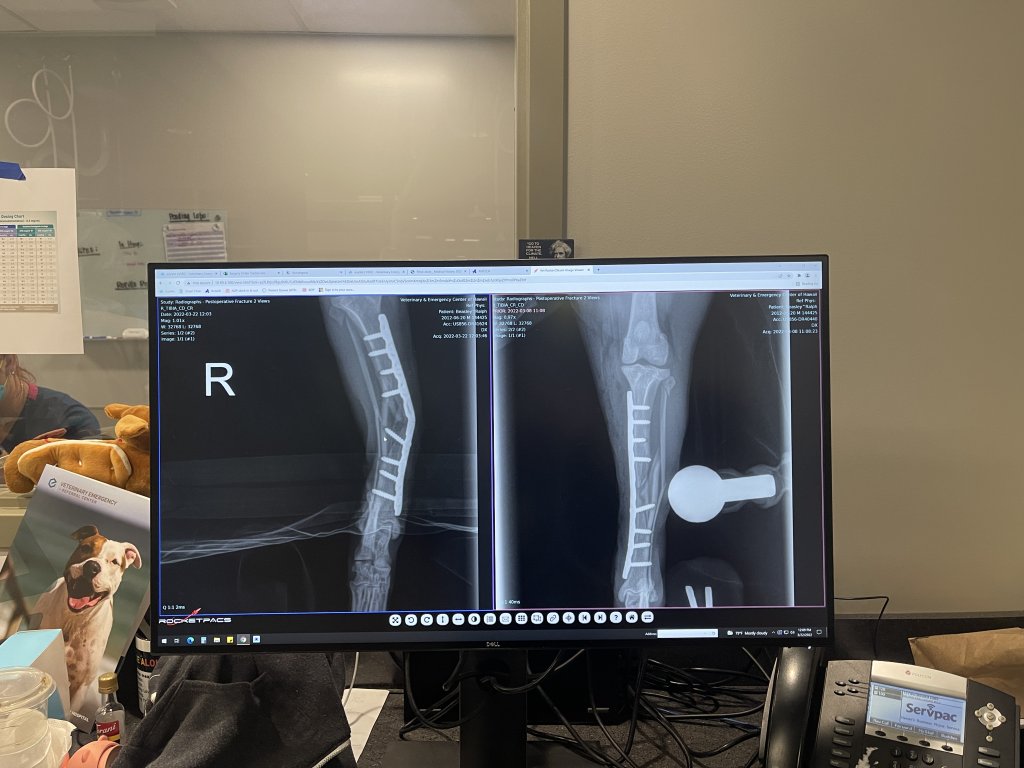

As some of you know, my daughter works at an emergency vet hospital. This is a surgery that she assisted on. The film on the right is immediately post-op, and the x-ray on the left is from the two-week follow up yesterday'ish (time zones be crazy, y'all). Sometime in the past two weeks (the owners "didn't know exactly when") this dog took an impact hard enough to bend the internal fixator. Notice that it is not the joint that is bent -- it is mid-limb. So, this poor doggo was hobbling around with what should have been a straight and immobile bone bent at a 30 degree angle... and the owners apparently didn't see anything wrong with it. This is why I don't like very many people.